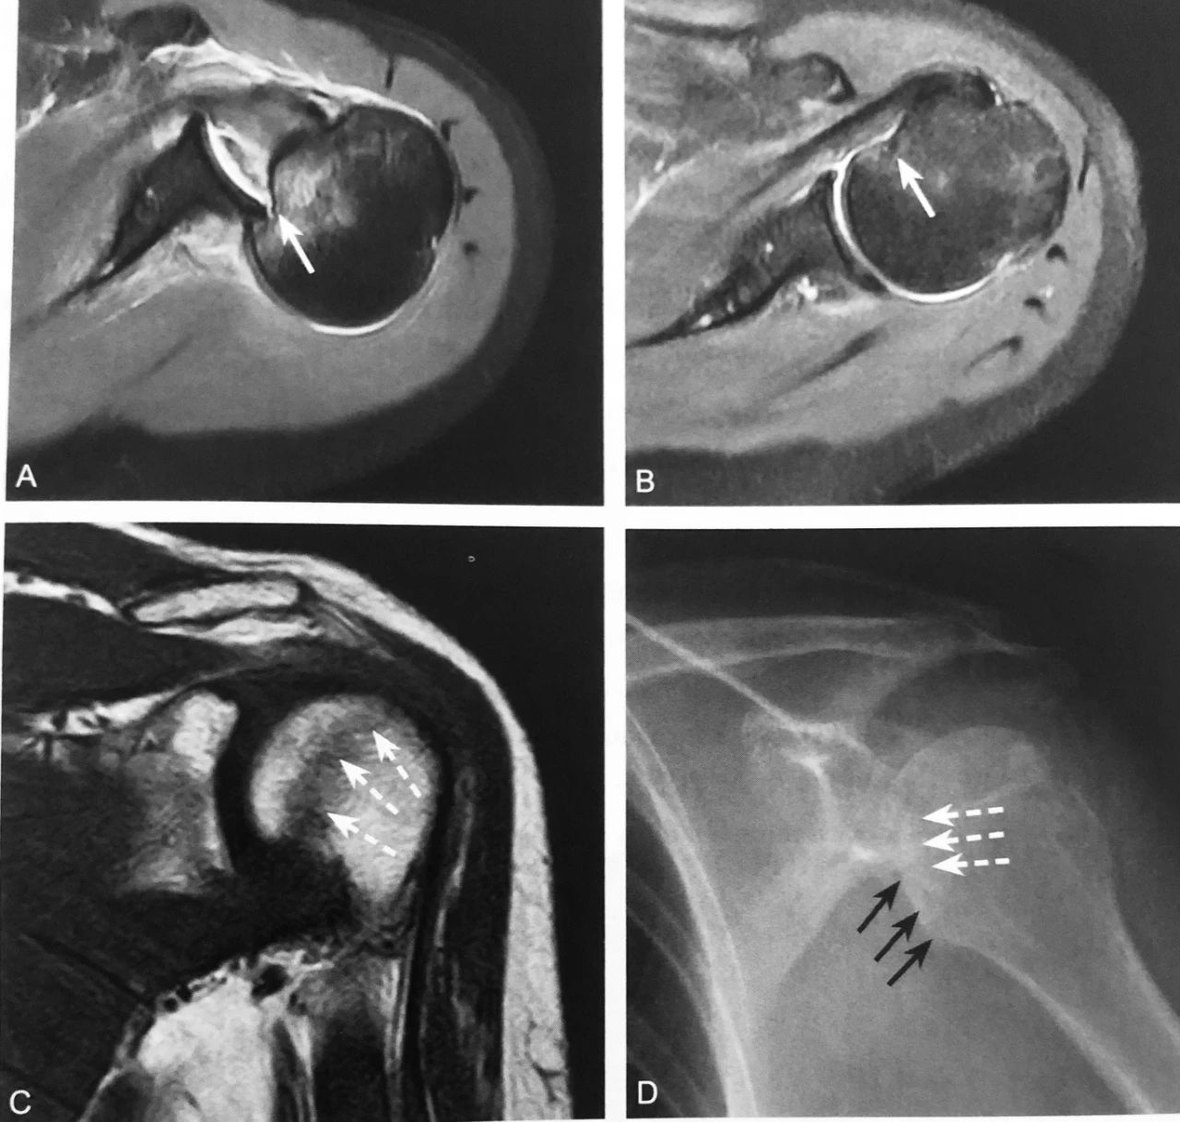

A、B 图为同一患者,抑脂 T2WI 示上盂唇周围两条线样高信号,其中一条高信号代表上盂唇的撕裂,另外一条指的是盂唇上隐窝,形成双曲奇饼征,提示上盂唇由前向后撕裂,即 SLAP 损伤(箭头所示)

判读要点:

1、SLAP 损伤的特征性表现;

2、在肩关节常规 MRI 斜冠状位 T2WI 或 MRI 关节造影图像显示,上盂唇内出现两条高信号;

3、具有较高的特异性,但敏感性较低。